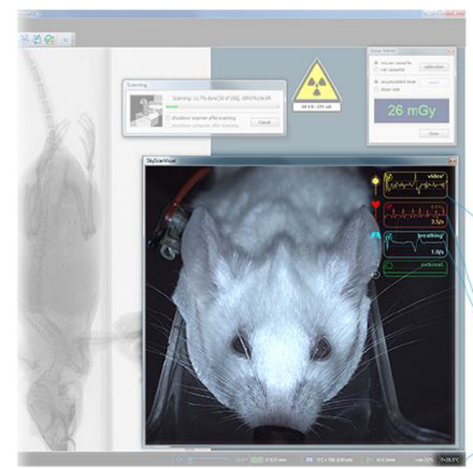

ON-SCREEN REAL-TIME DOSE METER

The SkyScan1278 control software includes a real-time on-screen dose meter. It indicates an estimation of the dose absorbed by the animal body during scanning. The measurement is based on the absorption calculated from X-ray projection images of the animal cross-calibrated with electronic dosimeter measurements. The dose meter shows accumulated dose or dose rate. It is calibrated for X-ray absorption in the standard mouse and rat cassettes. In this way it measures the X-ray dose absorbed in animal body itself during scanning. The dose absorbed by the animal during a scan is documented in the scan log-file together with all scan and reconstruction settings.

Integrated physiological monitoring

The physiological monitoring system includes video monitoring of an animal with real-time movement detection, ECG and breathing detection, and temperature stabilization. A 5 megapixel color camera is mounted above the animal bed along with white LED illumination to introduce a real-time image of the animal during the scan. The software analyses the video stream from a user-selected area of the image where breathing movement is visible. These movements are converted into a movement waveform to provide breathing time marks for time-resolved reconstructions. The face mask on the animal bed is connected to an air/gas flow sensor for direct breathing detection. The ECG electrodes in the animal cassette are connected to a sensitive ECG amplifier. Both breathing and ECG signals are digitized and displayed as real-time profiles on-screen. The monitoring also includes temperature stabilization by heated airflow, which maintains the scanned animal at a selected temperature, to prevent cooling of the animal under anaesthesia.